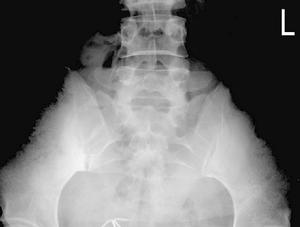

X線檢查:病變在骶髂關節的骼骨耳狀面上出現骨質呈均勻性密度增高,骨小梁消失,邊緣模糊,不侵犯關節面,病變寬度約0.5~3.0厘米,濃白實密徵象。其骨質硬化區構成各種不同的形態,大體上分為三角形、新月形、梨形三種。

X線所見:骶髂關節正位片見關節間隙整齊清晰,靠近骶髂關節面中下2/3的髂骨側骨質異常緻密呈均勻一致的骨質緻密帶,骨小梁紋理完全消失,邊緣清晰但無骨質破壞,不侵犯骶骨側。這種病變多為對稱性,也可發生於單側。局部可呈三角形,新月形或梨形。硬化區可寬達3cm。